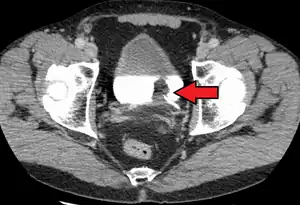

The most common sites for bladder cancer metastases are the lymph nodes, bones, lung, liver, and peritoneum.[76] The most common sentinel lymph nodes draining bladder cancer are obturator and internal iliac lymph nodes. The location of lymphatic spread depends on the location of the tumors. Tumors on the superolateral bladder wall spread to external iliac lymph nodes. Tumors on the neck, anterior wall and fundus spread commonly to the internal iliac lymph nodes.[77] From the regional lymph nodes (i.e. obturator, internal and external lymph nodes) the cancer spreads to distant sites like the common iliac lymph nodes and paraaortic lymph nodes.[78] Skipped lymph node lesions are not seen in bladder cancer.[77]